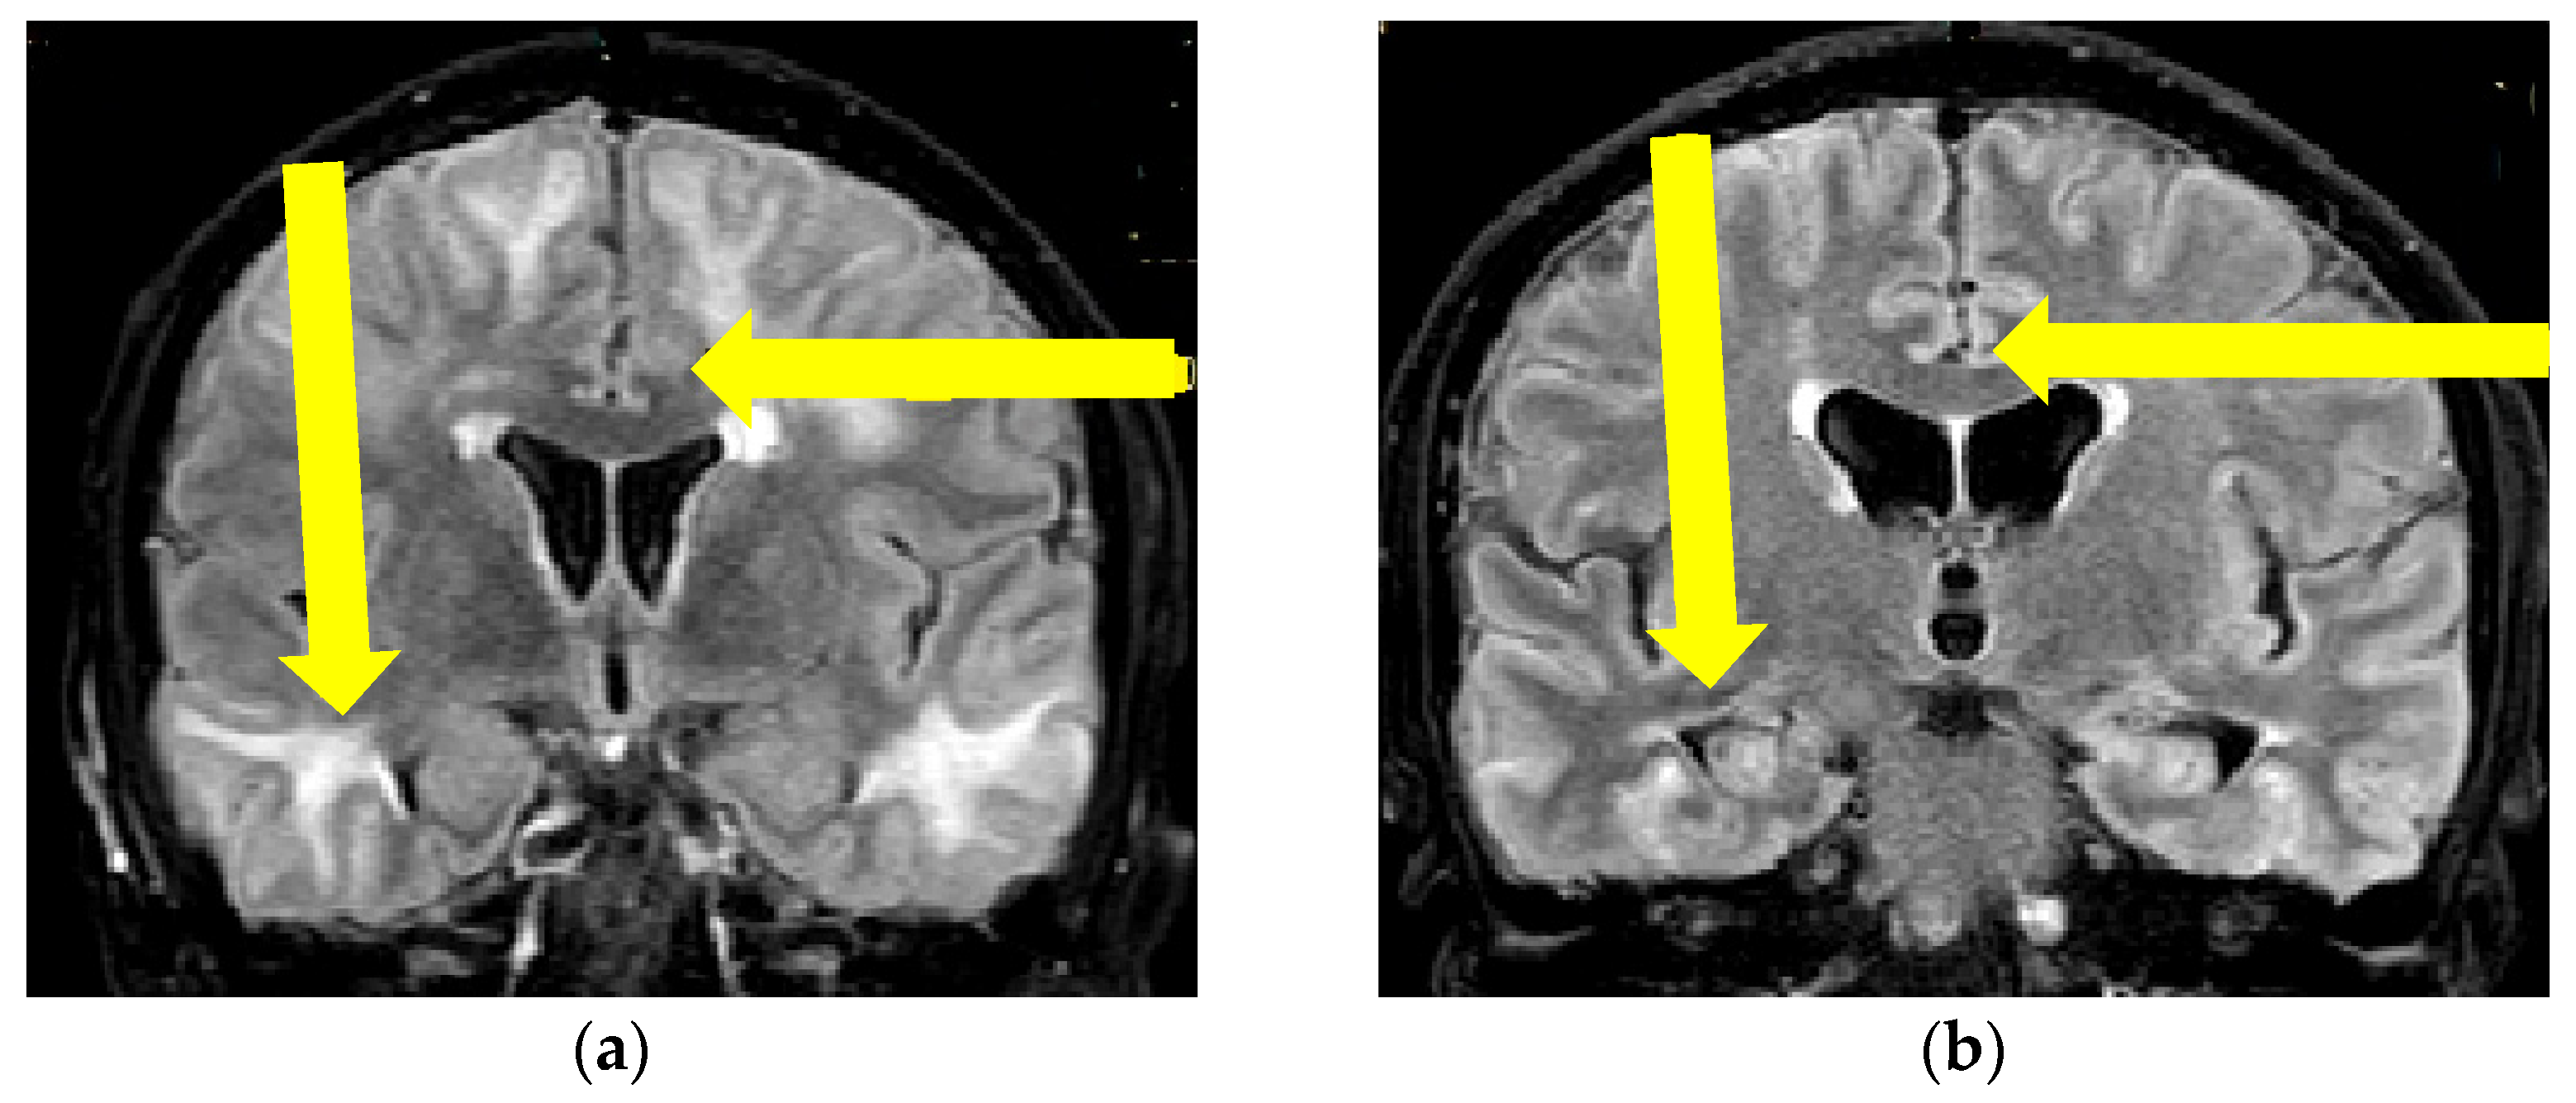

Figure 3.

Initial brain MR axial T2W sequence (a) and control MR examination three months after therapy initiation (b): (a) showing bilateral confluent hyperintense lesions, parieto-occipitally and temporally located in the cortex, subcortically and periventricularly, (b) shows confluent lesions subcortically, in the left temporal lobe in progression in comparison with previous images one month after therapy initiation. Yellow arrows showing confluent hyperintensities on the right parietally and on the left temporally (Patient No. 2).

Based on these findings a diagnosis of probable CAA-rI was established. Initially, pulse methylprednisolone (1 g/daily) therapy was administered for 5 days, followed by oral prednisone (1 mg/kg), slowly tapered down during the next 3 months. During the immunosuppressive treatment, our patient had a verified septic state but was successfully treated with intravenous antibiotic therapy. The follow-up MR examination one month after treatment initiation showed mild progression of the WMH lesions with the persistence of previously noted microbleeds (Figure 3 and Figure 4). Although her neurological examination was without focal neurological deficit, the patients was still complaining about the presence of headaches and her control neuropsychological assessment was mildly improved from the initial mini-mental state examination (MMSE) 22/30 to MMSE 23/30. Thus, treatment with oral prednisone (10 mg/daily) was reintroduced. The third follow-up MR examination after six months showed resolutions of the WMH lesions (not shown), while her neuropsychological assessment was further improving.